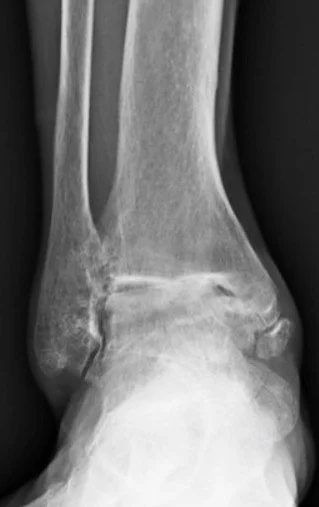

ap xray of severe post traumatic ankle arthritis

• Post-traumatic arthritis is most common. It can appear months or years after an ankle fracture or severe sprain, even if the injury seemed to heal well. Damage from the original trauma accelerates cartilage wear.¹ ² PMC